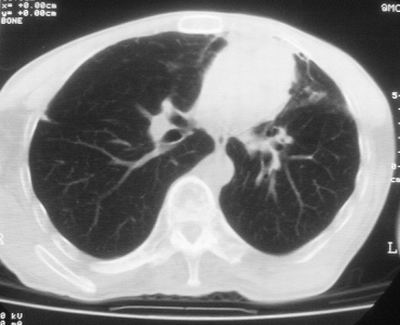

标题: CT11864:男,47岁,反复咳嗽、咯痰、咯血3年,请分析. [打印本页]

患者,男,47岁,反复咳嗽、咯痰、咯血3年,再发5天。痰培养未找到真菌、抗酸杆菌、癌细胞。

左肺上叶体积明显缩小,其内见多发透光区,纵隔向左侧移位,左肺下叶多发班片状病灶,边界模糊,1左肺上叶先天肺发育不全,2左肺下叶肺炎,

左肺上叶结核伴肺纤维化,纵隔移位,左肺下叶感染性病变,建议抗炎抗结核后复查,双肺气肿.

1)考虑为:左肺上叶肺结核(空洞形成),伴左下肺感染;不排除霉菌感染可能。2)肺气肿。

左肺上叶结核伴肺纤维化空洞形成并左肺下叶感染,纵隔牵拉移位,建议作进一步检查排除左侧肺霉菌感染可能。